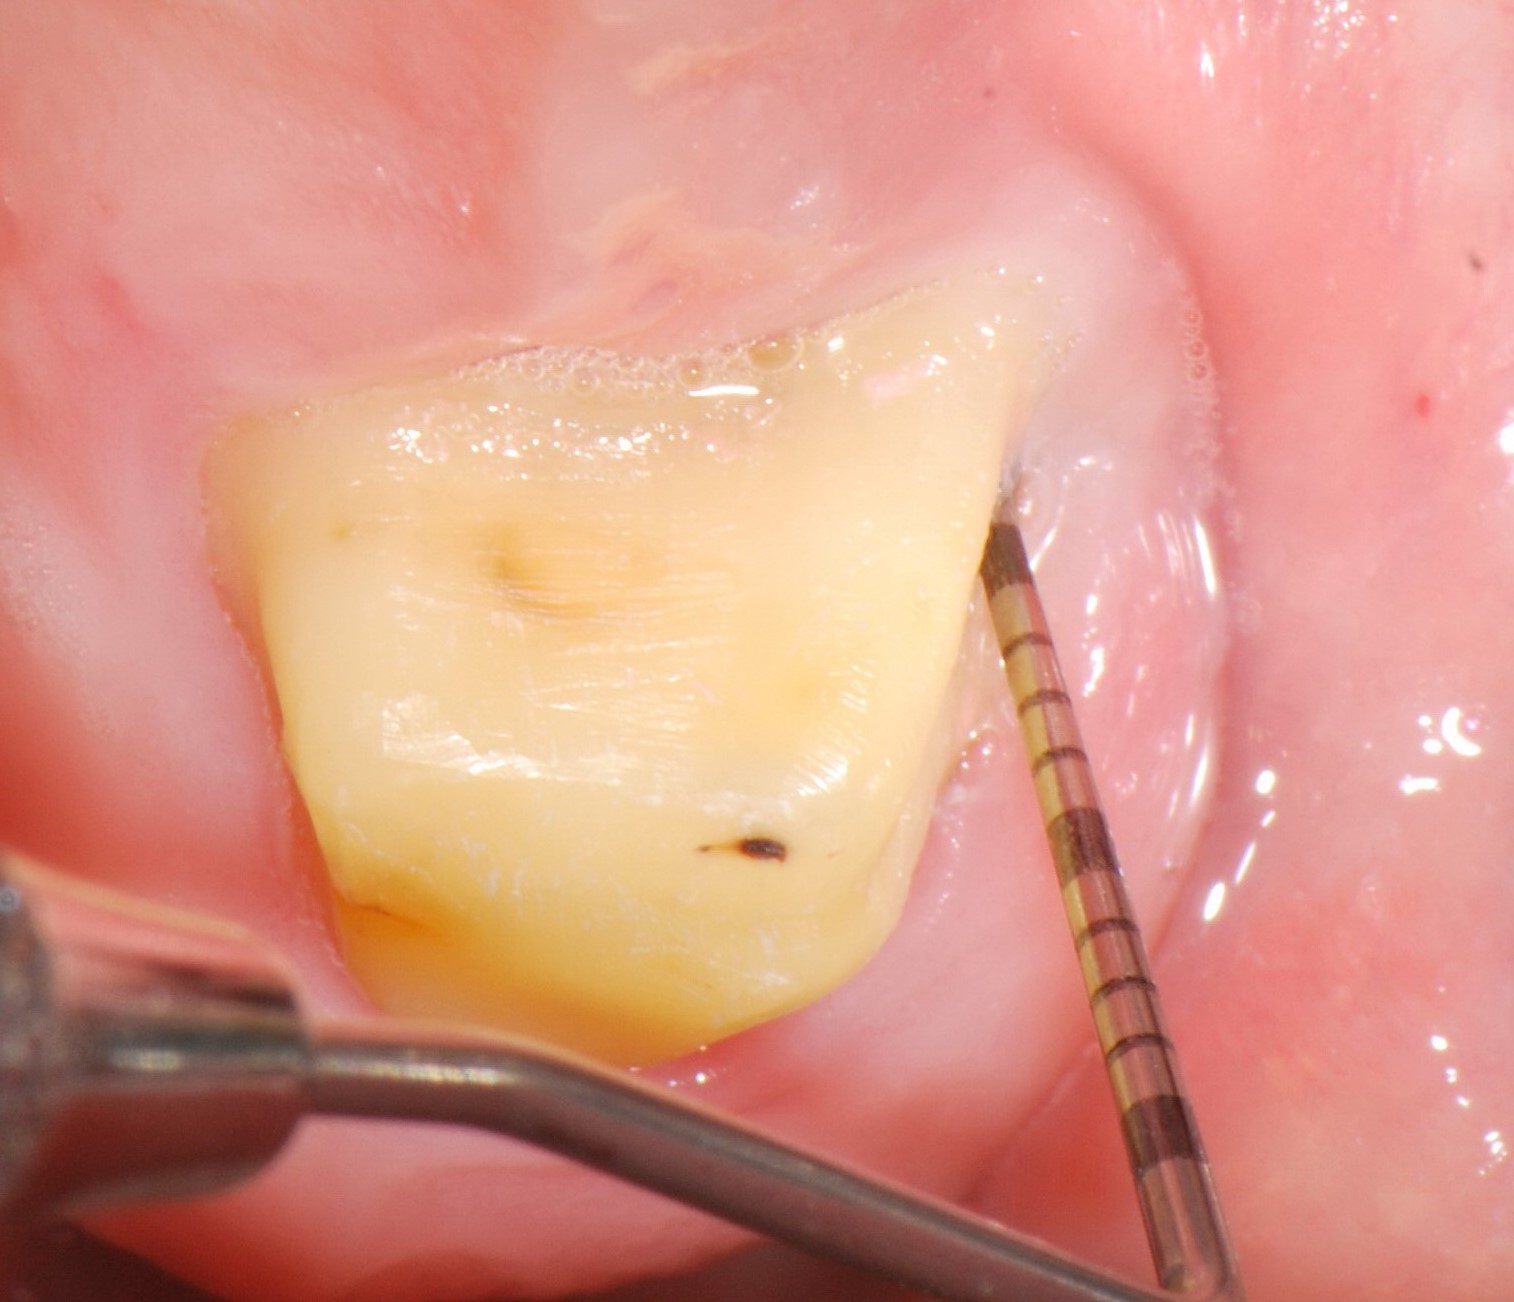

02/06 - Pre-surgical probing.

Treatment of a periodontal bone defect adjacent to an edentulous site using Straumann® Emdogain® - Prof. Dr. P. Windisch